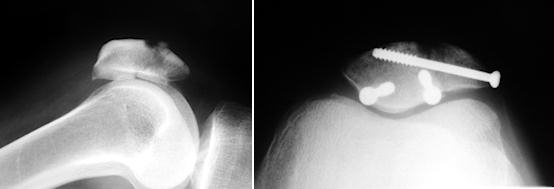

Seçilmiş bazı patella kırıkları, artroskopi destekli perkutan tespit için uygun olabilir. Bu olgularda, parçaların vaskülaritesi bozulmadan ve eklem yüzünün anatomik rekonstrüksiyonu artroskopi ile kontrol edilerek kırk tedavisi yapılabilir. Eklem yüzünün anatomik redüksiyonunu gerektiren kırık deplasmanı olan ancak ekstansör mekanizma bütünlüğünün korunmuş olduğu hastalarda artroskopi destekli tespit yapılabilir. Bu pratik olarak 6-8 mm deplasmanı olan hastalar demektir. Ayrıca, fragmanların vida tespitine izin verecek kadar büyük olması gerekir. Buna karşın, ekstansör mekanizma devamlılığın bozulduğu hastalarda, kırık tespitine ek olarak ekstansör mekanizmanın da tamiri gerekir. Bu olgular, artroskopi destekli tedavi edilemezler ve kırığın açık tespitine ek olarak, medial ve lateral retinaküler yapıların açık tamiri de gereklidir.Cerrahi teknik

Perkutan yerleştirilen 2 paralel K-teli ile geçici tespit sağlanır. Skopi kontrolü sonrası, K-telleri üzerinden kanüllü matkap uçları ile vida yolları hazırlanır ve 4.0 mm kanüle vida ile kalıcı tespit yapılır.

Sadece transvers kırıklar değil, fragmanlar yeteri kadar büyük ise, çok parçalı kırıklar da bu yöntem ile tedavi edilebilir. Genç ve kemik stoğu iyi olan hastalarda vida tespiti, gergi bandı yöntemi kadar etkindir (Benjamin J. J Orthop Trauma 1987, 1:219-22).